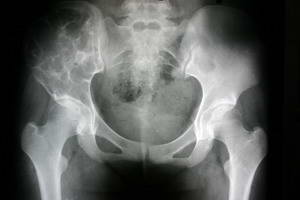

動脈瘤樣骨囊腫--X片平片示:①偏心型:發生於長骨的多為此型,病灶偏於骨幹的一側,呈吹氣臌樣膨出至骨外,內有骨性間隔,似蜂窩狀。②中心型:呈溶骨性囊狀透明影,最大直徑可達10cm。囊內含有粗細不均的骨性間隔,呈多房狀,向橫的方向擴張。③位於扁骨時,病灶呈囊狀膨脹。位於脊柱者除呈囊狀膨脹外還可跨越椎間盤,侵入鄰近椎體。動脈瘤樣骨囊腫如發生於椎體等少見的短管骨,X線檢查應注意與骨囊腫、巨細胞瘤、血管瘤、孤立性內生軟骨瘤和囊狀骨纖維結構不良等鑑別。上述各病均可引起短骨囊狀骨質破壞,骨皮質膨脹變薄,其內呈蜂房狀,但骨囊腫、孤立性內生軟骨瘤和囊狀骨纖維結構不良病變的膨脹程度多不如動脈瘤樣骨囊腫,也多無本病所見的典型的皂泡樣改變。血管瘤具有典型的柵欄狀骨質改變,病灶內鈣化,以及MRI信號,血管瘤燈泡征特性和慢進慢出的強化表現。孤立性內生軟骨瘤雖好發於手足短管骨,但以手部發病率為高,多位於乾骺或骨幹內,呈輕度膨脹,易骨折,特徵性表現為囊內有瘤軟骨的鈣化,骨囊腫病灶內部多無骨嵴分隔及鈣化;單囊型骨纖維結構不良X線多呈較特徵性的毛玻璃樣改變,纖維組織易鈣化及骨化,多有硬化邊。對於少數影像學近似病例,傳統X線診斷難以定性,多需要CT或MRI進一步檢查。

(1)孤立性骨囊腫:多見於四肢長骨,常為中心型,呈對稱性輕度膨脹的骨壞死,周圍為緻密硬化帶。囊壁外緣光滑整齊,內緣則不光整。隨骨骼生長逐漸移向骨幹,常因病理骨折而發現。

(2)巨細胞瘤:發病年齡較大,病變多位於長骨端的關節下方,關節面常為腫瘤的部分輪廓,由於腫瘤縱行、橫行生長差不多,故腫瘤多呈球形。瘤內有皂泡狀陰影。骨化及反應性骨硬化現象少見。而動脈瘤樣骨囊腫發病較輕,病變多位於乾骺端,很少侵犯骨骺。常有不同程度的骨硬化現象。